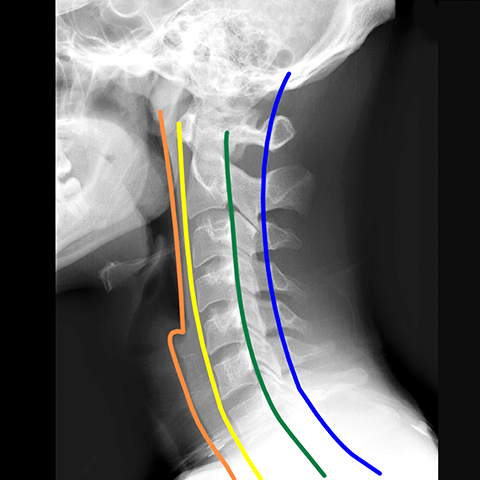

Cervical Spine, plain film (oblique view) [5 of 8]

Lines

Lines and Labels